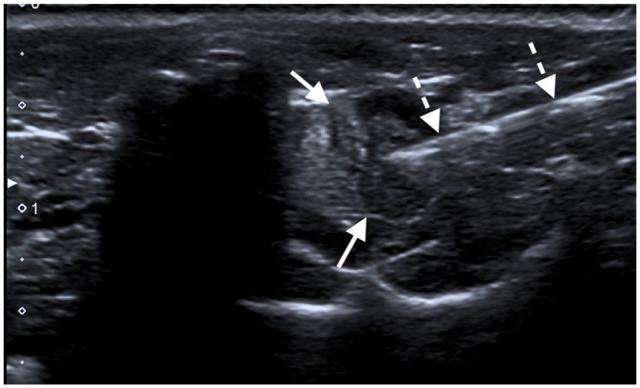

A 9-year-old male neutered European Shorthair cat was presented owing to vomiting and mild weight loss. Clinical examination was normal, but biochemistry results showed increased concentrations of total calcium (4.05 mmol/l; reference interval [RI] 2.20-2.90 mmol/l) and ionised calcium (iCa) (2.19 mmol/l; RI 1.12-1.40 mmol/l), as well as hypophosphataemia (2.5 mg/dl; RI 3.1-7.5 mg/dl). Parathyroid hormone (PTH) concentration (>1000 pg/ml) was markedly increased, while parathyroid hormone-related protein concentration (<0.8 pmol/l) was normal. Neck ultrasound showed a large left parathyroid mass (13 × 7 × 6 mm). Under general anaesthesia and with ultrasonographic guidance, a fine-needle aspiration of the mass followed by chemical ablation with 2 ml 96% ethanol was performed. The cat was re-evaluated and iCa concentration measured 24 h, 72 h, 5 days, 4 weeks and 4 months post-ablation. Normocalcaemia was reached within 24 h, remained stable throughout the whole evaluation period and the concentration of PTH normalised 4 months later. Vomiting stopped promptly after chemical ablation and a slight change in voice, as well as a mild prolapse of the nictitating membrane, were the only side effects after the treatment but resolved some weeks later.

一只9岁已绝育的欧洲短毛雄性猫因呕吐和轻度体重减轻前来就诊。临床检查正常,但生化检查结果显示总钙浓度升高(4.05 mmol/L;参考区间[RI] 2.20 - 2.90 mmol/L)、离子钙(iCa)浓度升高(2.19 mmol/L;RI 1.12 - 1.40 mmol/L)以及低磷血症(2.5 mg/dl;RI 3.1 - 7.5 mg/dl)。甲状旁腺激素(PTH)浓度显著升高(>1000 pg/ml),而甲状旁腺激素相关蛋白浓度正常(<0.8 pmol/L)。颈部超声显示左侧甲状旁腺有一个较大肿块(13×7×6 mm)。在全身麻醉和超声引导下,对肿块进行细针穿刺,随后用2 ml 96%乙醇进行化学消融。在消融后24小时、72小时、5天、4周和4个月对猫进行重新评估并测量iCa浓度。消融后24小时内血钙恢复正常,在整个评估期内保持稳定,4个月后PTH浓度恢复正常。化学消融后呕吐立即停止,治疗后唯一的副作用是声音略有变化以及瞬膜轻度脱垂,但几周后症状消失。